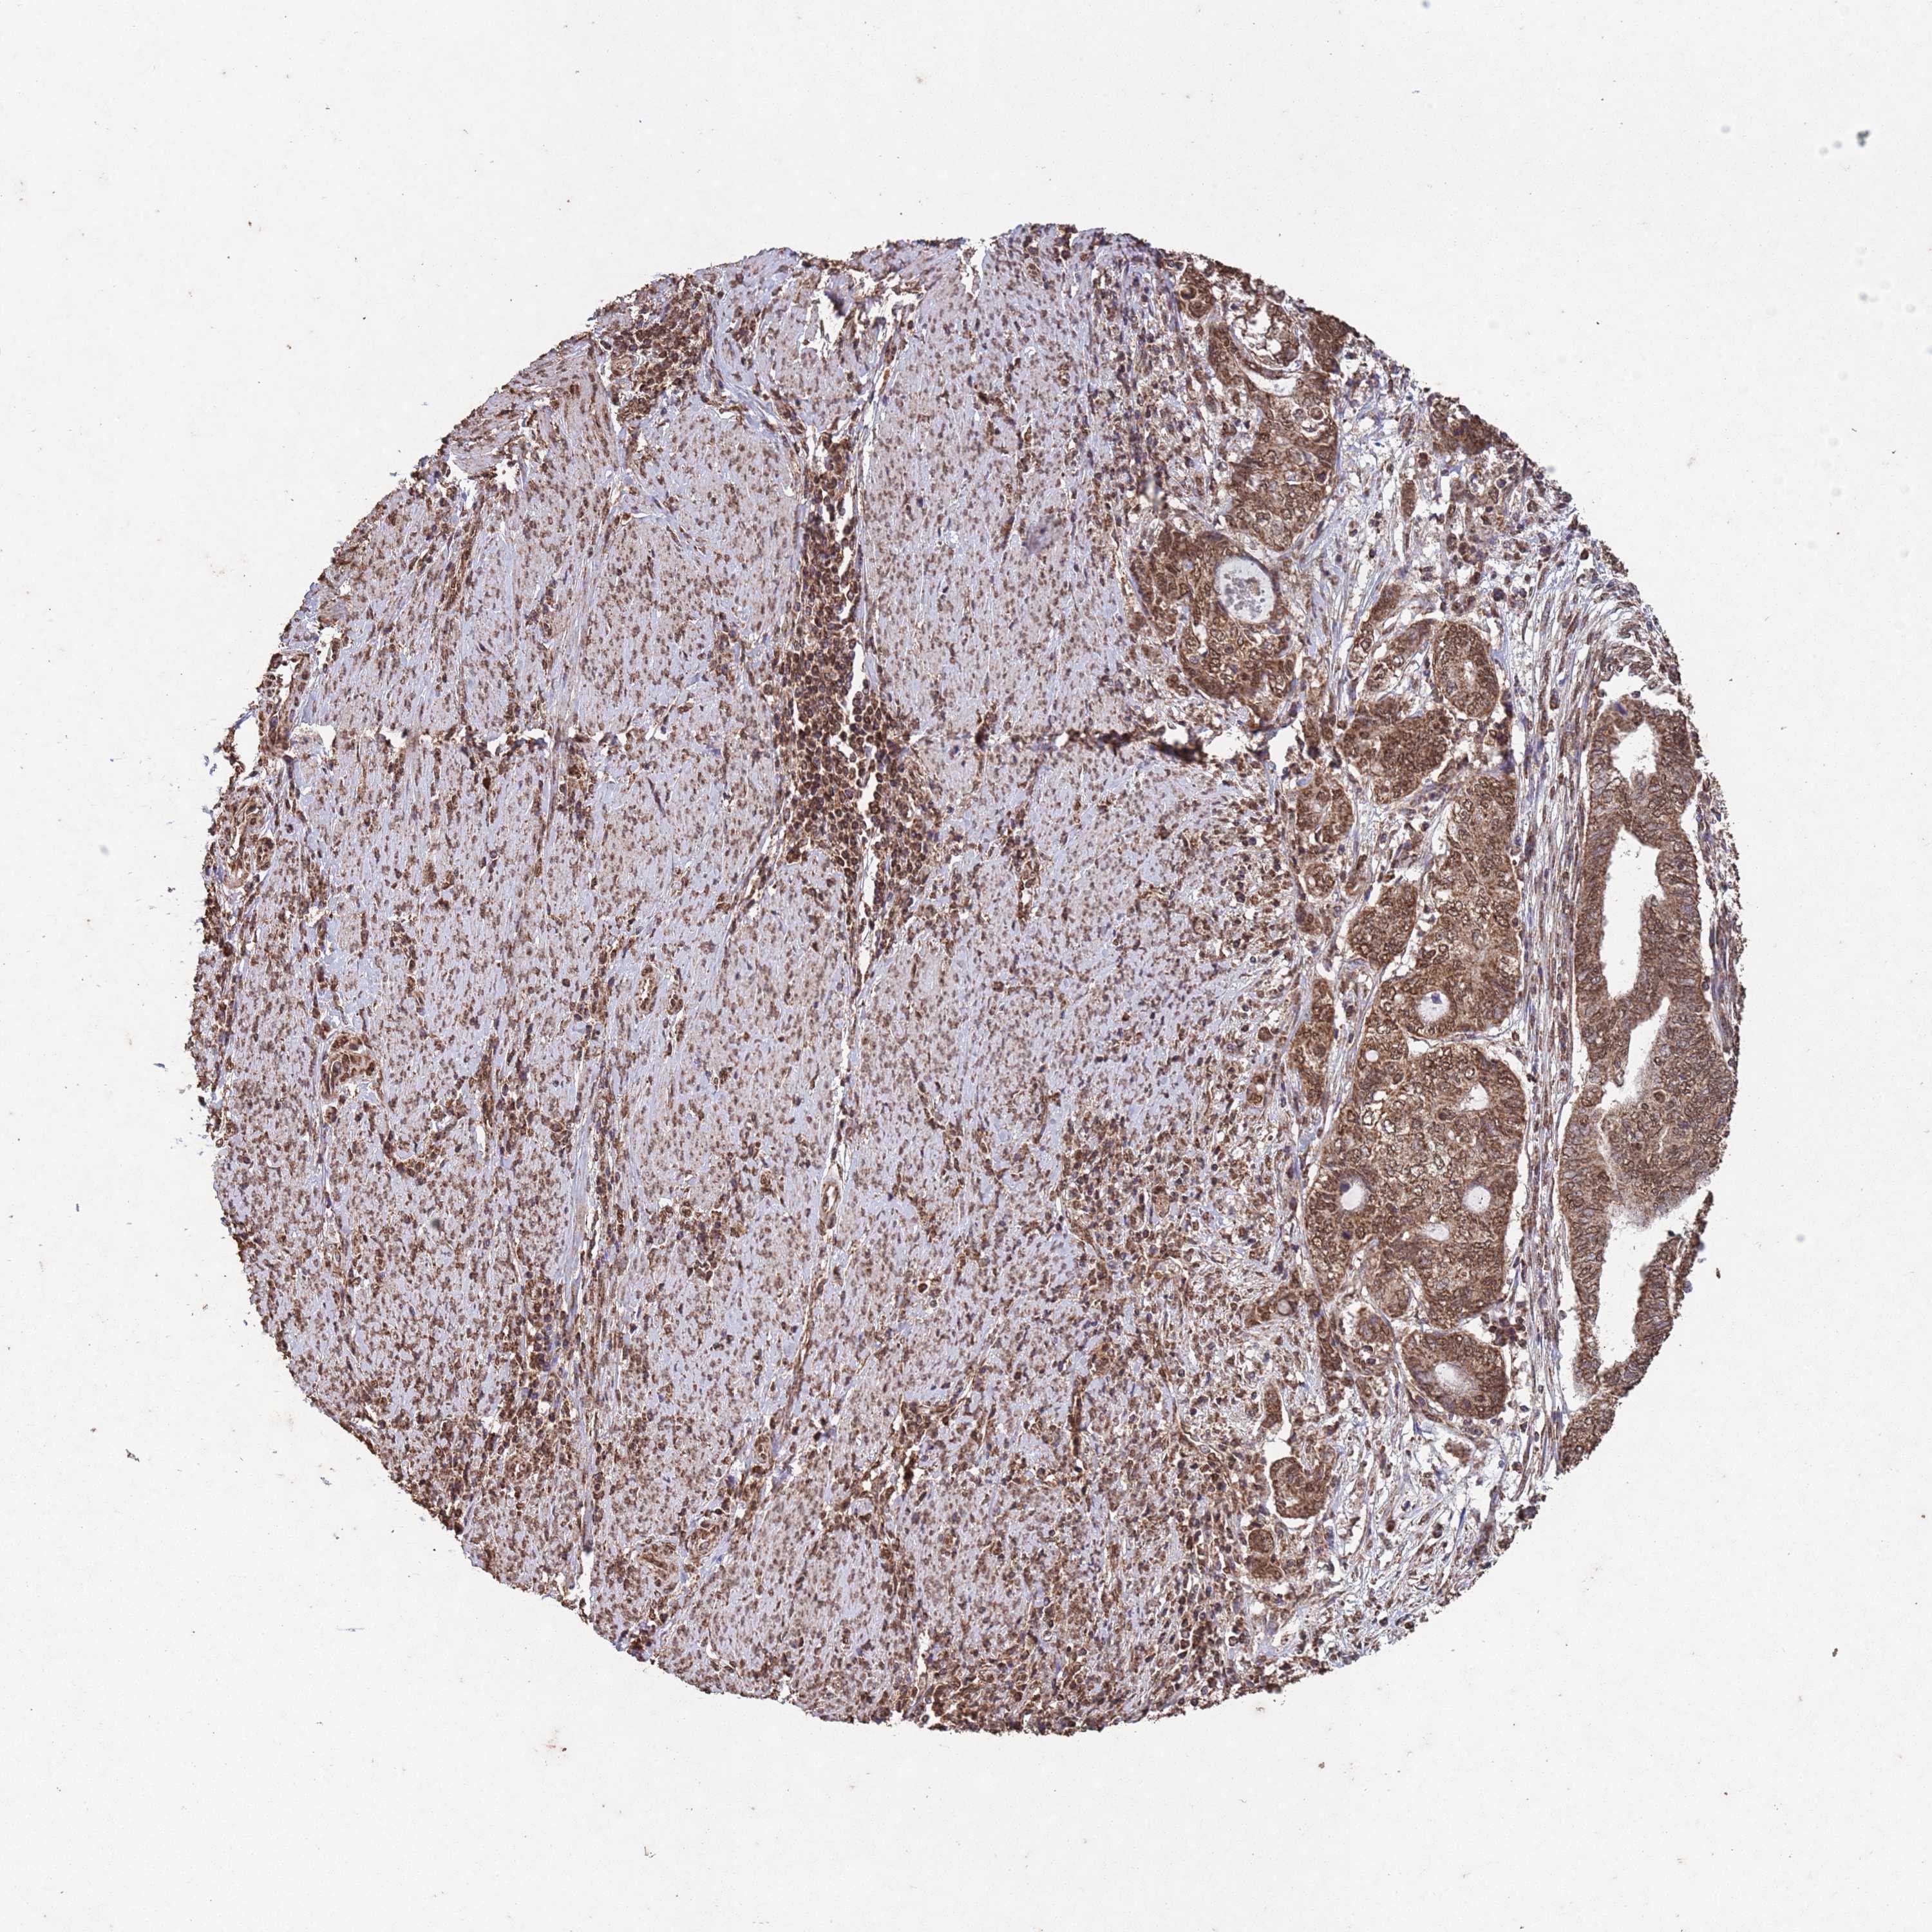

ENDOMETRIAL CANCER - Protein expressioni

A mouse-over function shows sample information and annotation data. Click on an image to view it in a full screen mode. Samples can be filtered based on level of antibody staining by selecting one or several of the following categories: high, medium, low and not detected. The assay and annotation is described here.

Note that samples used for immunohistochemistry by the Human Protein Atlas do not correspond to samples in the TCGA dataset.

Antibody stainingi

Antibody staining in the annotated cell types in the current human tissue is reported as not detected, low, medium, or high, based on conventional immunohistochemistry profiling in selected tissues. This score is based on the combination of the staining intensity and fraction of stained cells.

Each image is clickable and will lead to virtual microscopy that enables deeper exploration of all samples and also displays staining intensity scores, fraction scores and subcellular localization as well as patient and tissue information for each sample.

Antibody CAB045977

Staining

High

Medium

Low

Not detected

Intensity

Strong

Moderate

Weak

Negative

Quantity

>75%

75%-25%

<25%

None

Location

Nuclear

Cytoplasmic/membranous

Cytoplasmic/membranous,nuclear

Adenocarcinoma, NOS